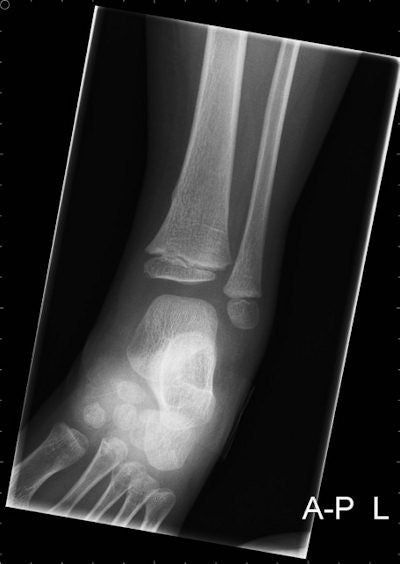

Children sitting on the rear of a bicycle, without proper safety precautions, are particularly prone to this type of injury, which occurs most often in children under the age of 14, with a peak incidence between 2 and 6 years of age. In more than 30% of the cases, a fracture may be apparent on radiographs, and in almost all patients the fracture is located at the distal tibia or fibula, noted radiology resident Annelie Slaar, earning her PhD, and colleagues from the Academic Medical Center at the University of Amsterdam.

In almost two-thirds of the patients (63%), radiography of two or more anatomical regions was performed. In 98 children (99%), the fracture was located at the distal tibia or fibula. All fractures were diagnosed on a radiograph of the ankle or lower leg (including the ankle region). No fractures of the foot were diagnosed.

There were 158 (49.4%) male patients with a mean age of 4.2 years (SD, 1.8). A total of 99 patients had a fracture, of which 48 patients were male. The peak incidence of both a bicycle spoke injury and a fracture was at 4 years of age. In all patients with a fracture, in whom a radiograph of the ankle and the lower leg was obtained, the fracture was visible on both the radiograph of the ankle and the lower leg.